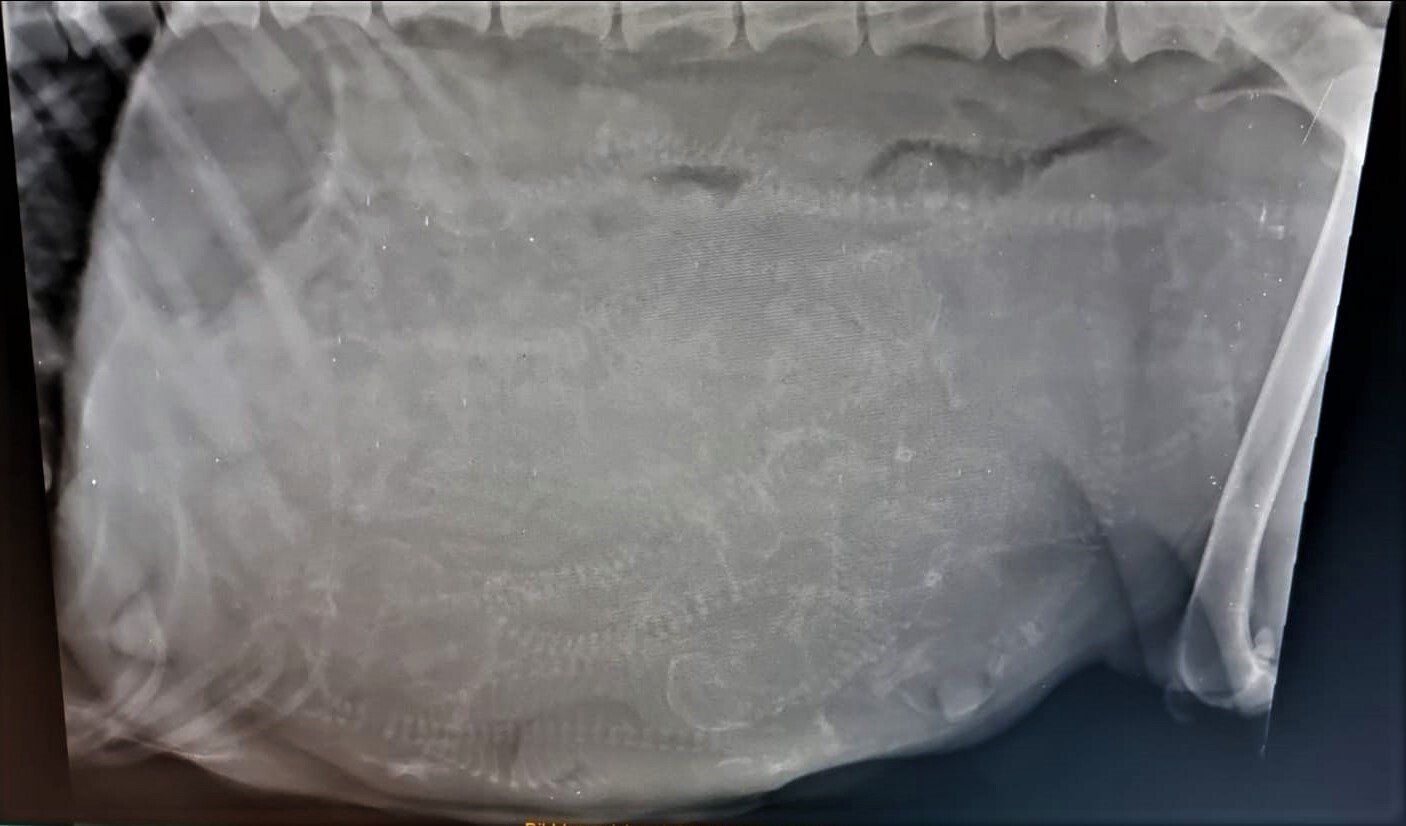

Heute waren wir mit Cleo beim Tierarzt um die obligatorische Röntgenuntersuchung durchführen zu lassen. Alles ist bestens verlaufen, wir hatten anschließend viel Spaß beim Versuch die Anzahl der Welpen auf dem Röntgenbild zu bestimmen.